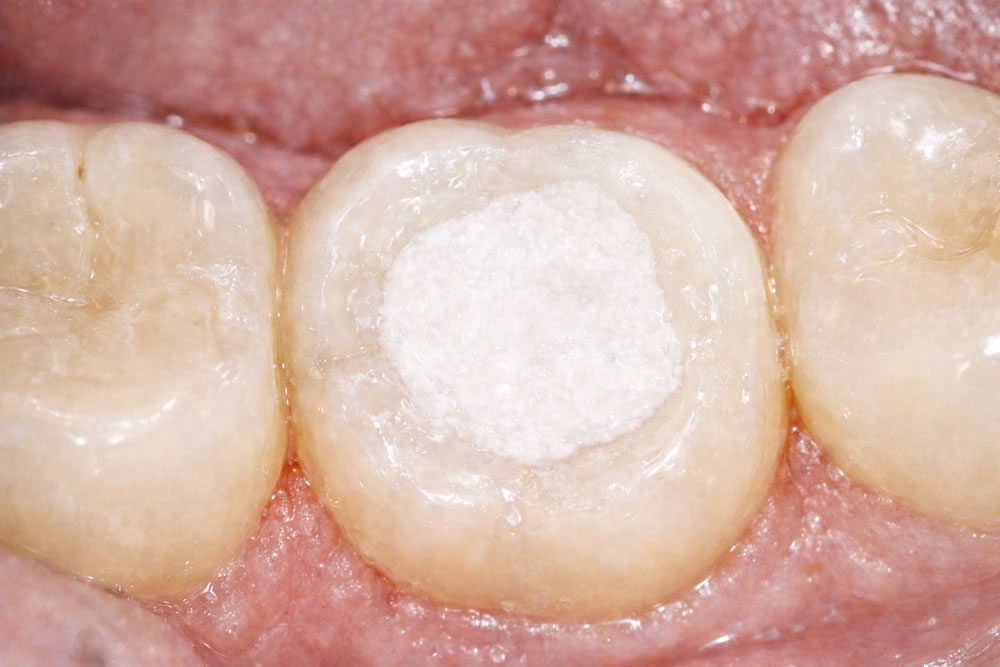

下記に、患者さまのご協力のもと神経治療(根管治療)の時の写真をアップしました!みなさまの疑問なことの解決の役に立てればと思いました。

①奥歯を上から見たところです。(鏡に反射した絵を見ながら治療してます)

②色々と汚れを取りました。上の写真と比べると神経の入っていた穴が丸でないことにご注目ください。(でも、防腐剤は、丸い形なので隙間ができる可能性あり!!!)

③気合いを入れて1時間治療しました。しかし、まだ、汚れが残っていました!悔しい!次回もしつこく治療します!少し、ご理解頂けましたか?